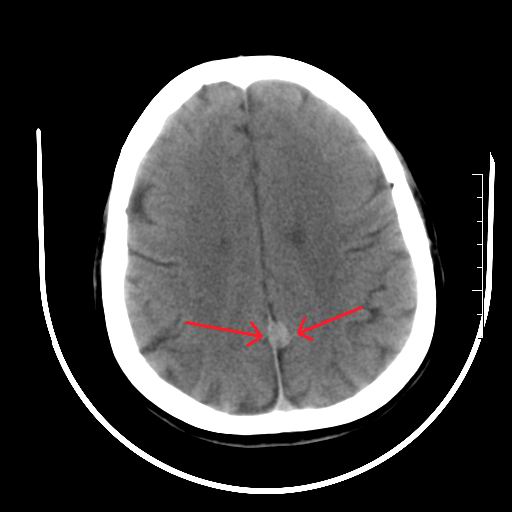

标题: CT27880:f、55y,头痛。 [打印本页]

标题: CT27880:f、55y,头痛。

考虑左侧顶部镰旁脑膜瘤;建议行ct增强扫描检查。

考虑左侧顶部镰旁脑膜瘤,建议行ct增强扫描检查。

考虑左侧顶部镰旁脑膜瘤;建议行ct增强扫描检查

大脑镰旁脑膜瘤可能,建议增强或mri

镰旁小脑膜瘤可能性大

左侧顶部镰旁脑膜瘤,增强